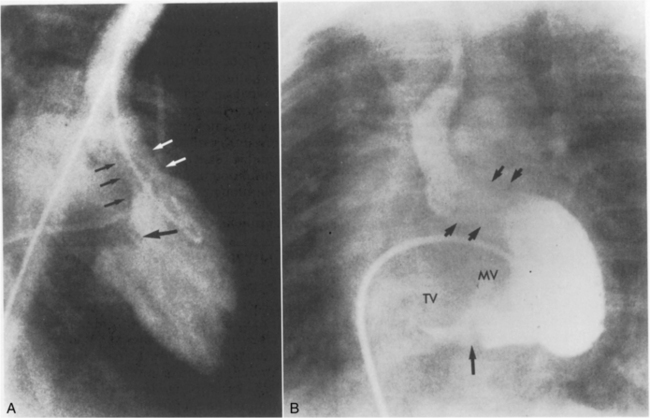

Table 8-25 Clinical, Radiographic and Electrocardiographic Characteristics of Acyanotic Congenital Heart Defects

image